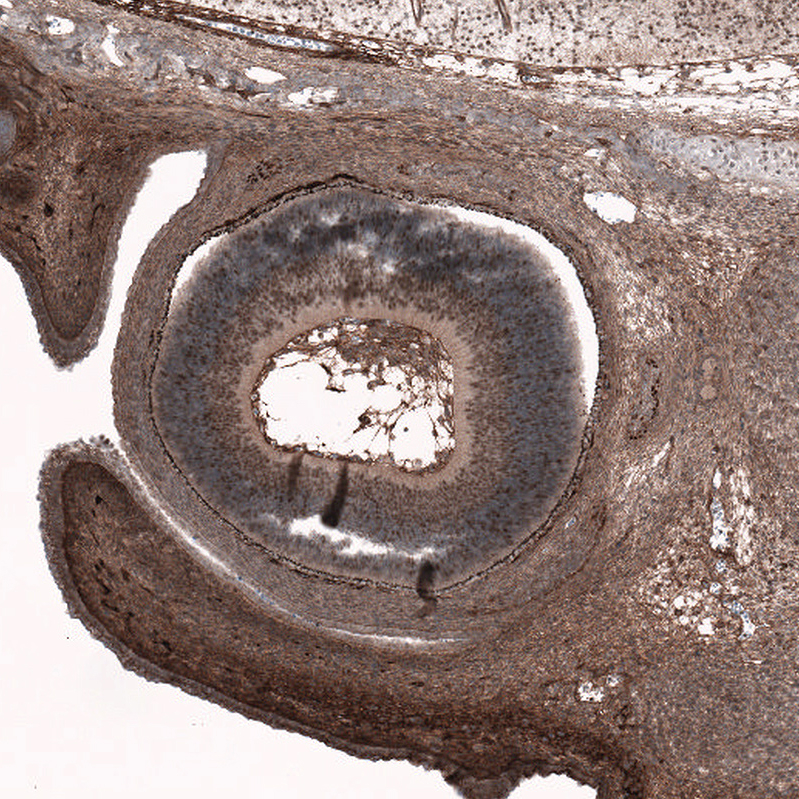

Immunohistochemical staining of human mantle cell lymphoma shows moderate to strong nuclear positivity in tumor cells.